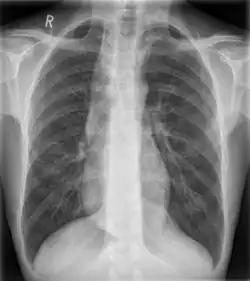

![]() | |

Widened mediastinum in a patient with achalasia |

Widened mediastinum/mediastinal widening is where the mediastinum has a width greater than 6 cm on an upright PA chest X-ray or 8 cm on supine AP chest film.[11]

A widened mediastinum can be indicative of several pathologies:[12][13]

- aortic aneurysm[14]

- aortic dissection[15]

- aortic unfolding

- aortic rupture

- hilar lymphadenopathy

- anthrax inhalation - a widened mediastinum was found in 7 of the first 10 victims infected by anthrax (Bacillus anthracis) in 2001.[16]

- esophageal rupture - presents usually with pneumomediastinum and pleural effusion. It is diagnosed with water-soluble swallowed contrast.

- mediastinal mass

- mediastinitis

- cardiac tamponade[17]

- pericardial effusion

- thoracic vertebrae fractures in trauma patients.